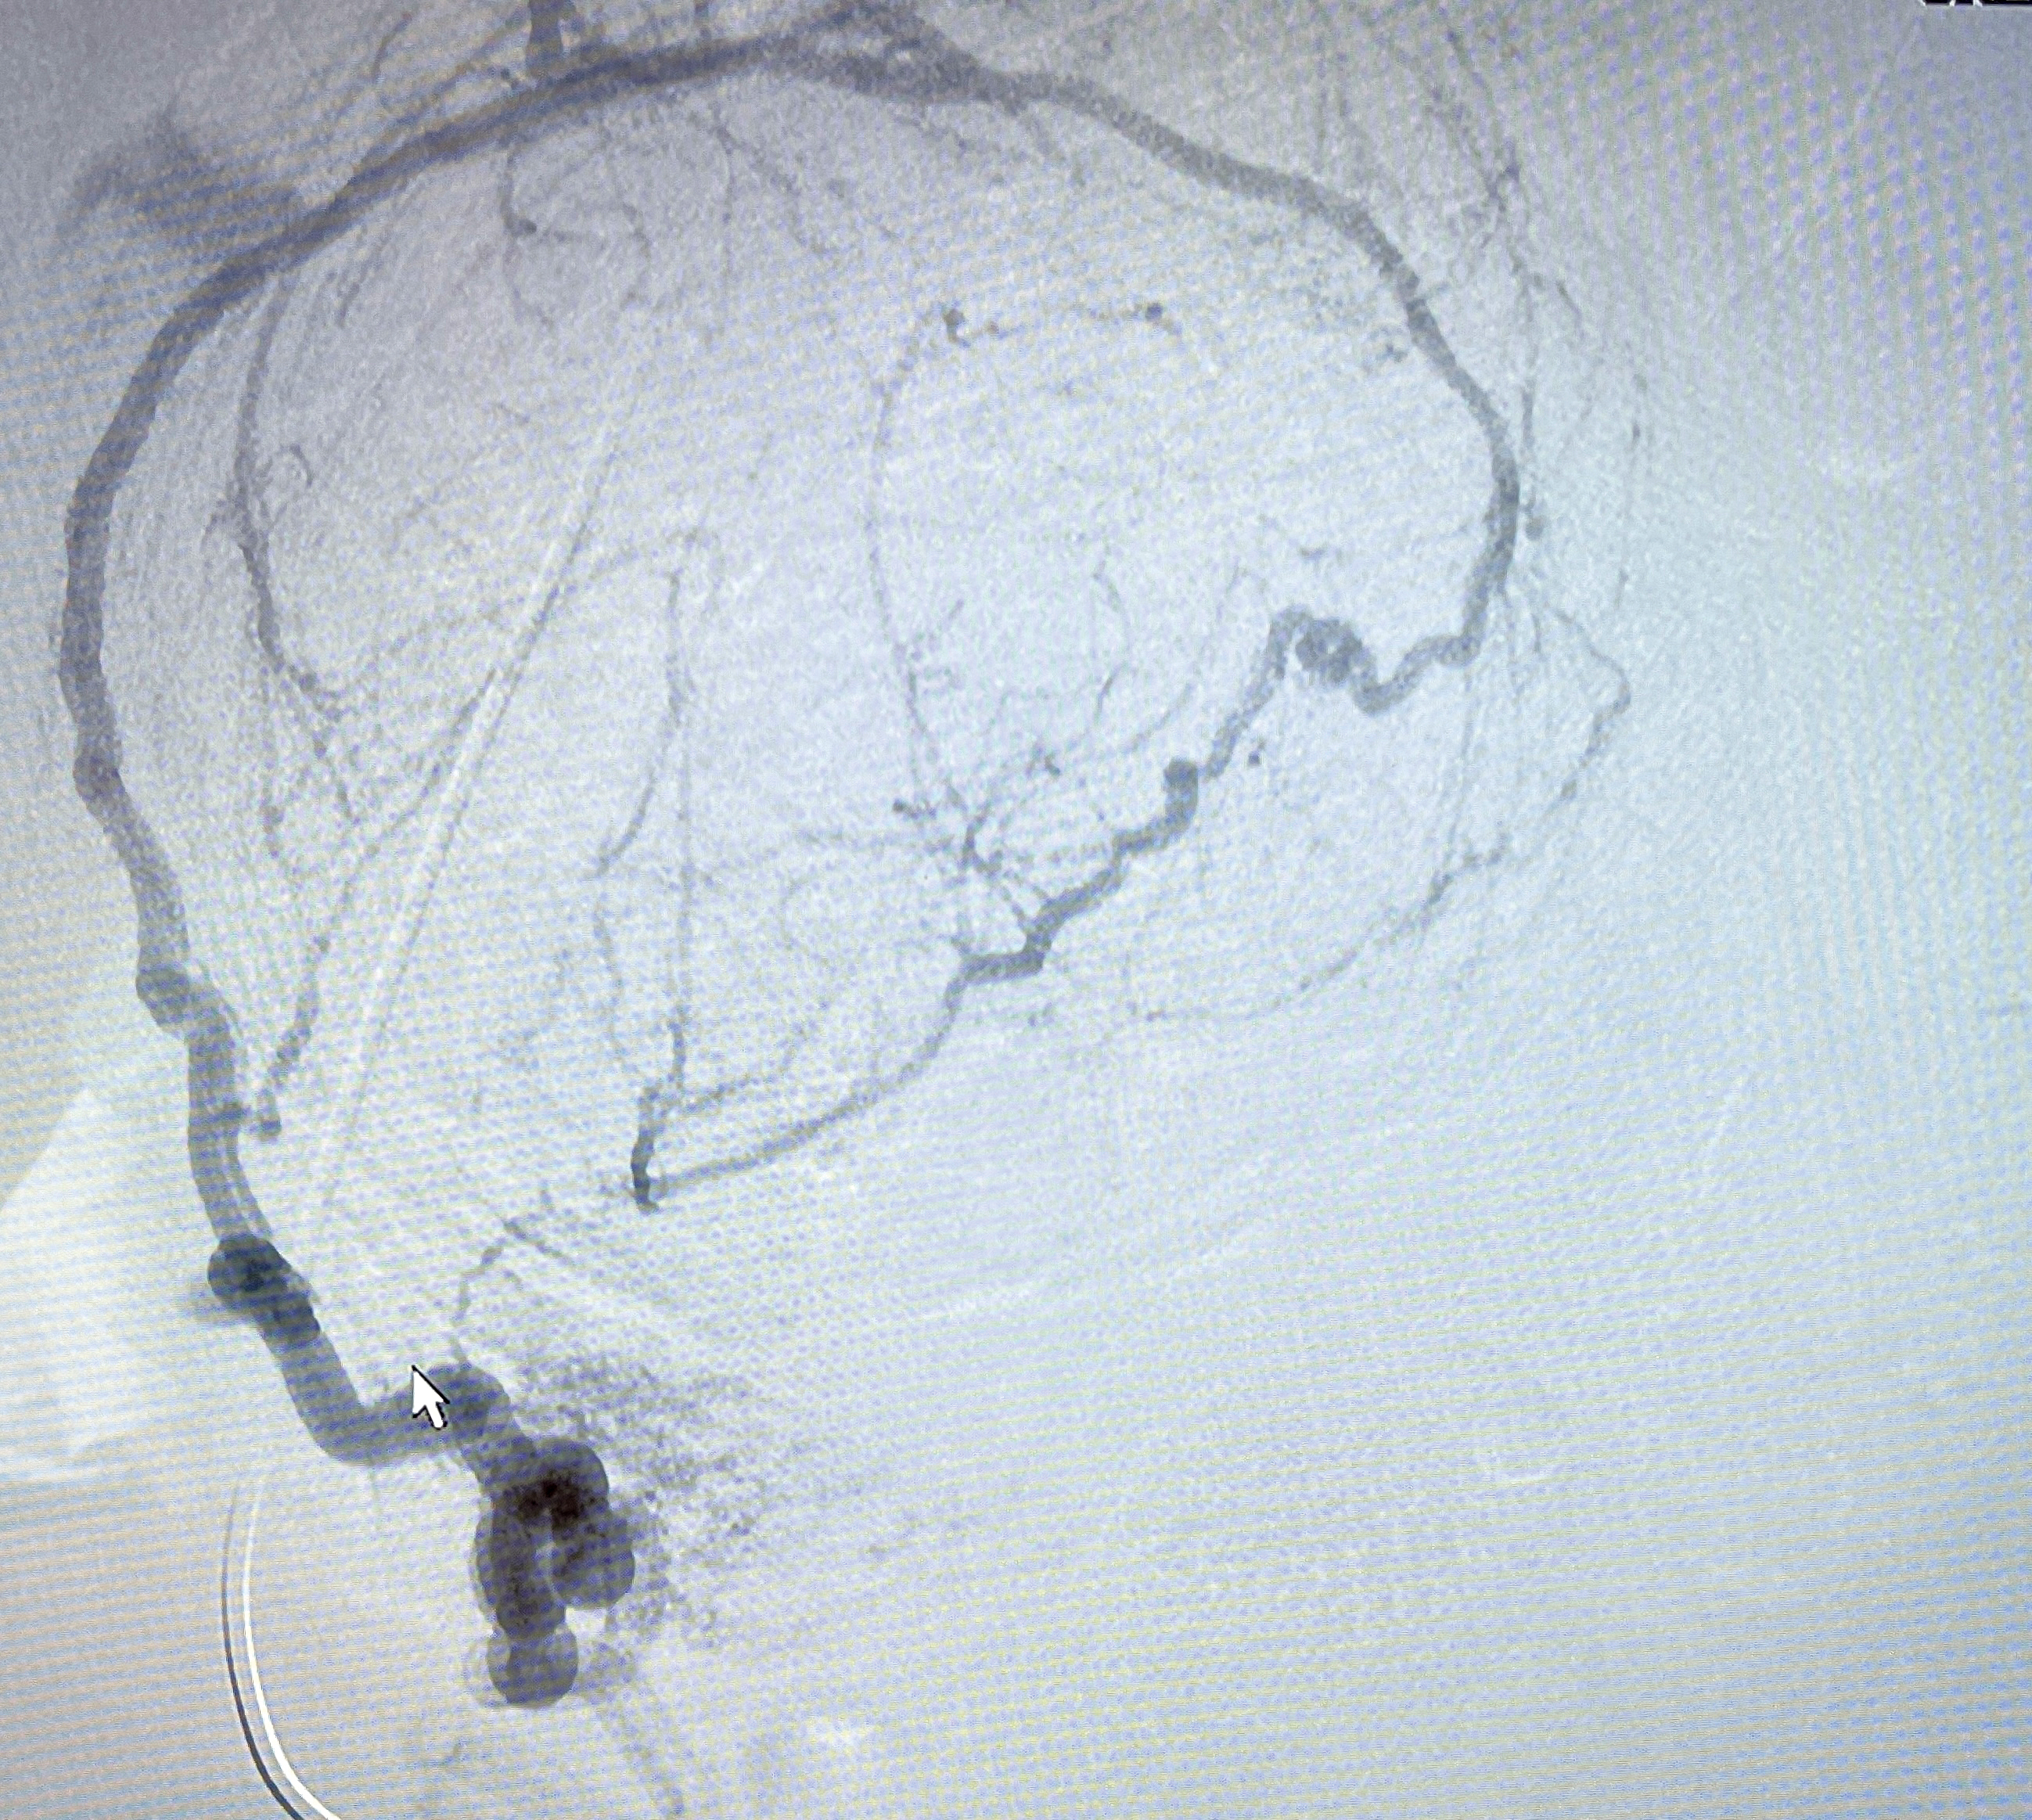

В региональном сосудистом центре Городской клинической больницы имени М. П. Кончаловского давно и успешно применяют высокие технологии. Эмболизация маточных артерий – один из широко используемых методов внутрисосудистой хирургии. Он позволяет сохранить репродуктивные функции и не требует длительного восстановления после операции. Общий наркоз не нужен, достаточно местной анестезии, чтобы сделать прокол, через который вводится тонкий катетер. С его помощью под контролем рентгеновского оборудования в артерию подают специальные микрочастицы. Они закупоривают сосуды, питающие миому. Кровь не поступает в ткани, и патологические клетки постепенно погибают.

«Через лучевую артерию поочерёдно подвели катетер к правой и левой маточным артериям и ввели специальный эмболизат, который заблокировал кровоток в миоматозных узлах. В данном случае мы вводили микросферы. Это микроскопические шарики (эмболы) разных размеров. Так как у пациентки были крупные узлы, нам понадобилось пять доз эмболизата. Операция длилась около часа», – рассказал эндоваскулярный хирург Городской клинической больницы имени М. П. Кончаловского Евгений Боровков.